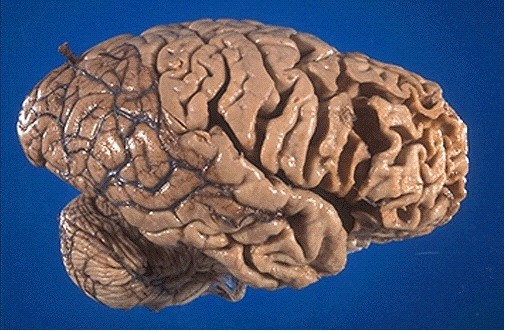

Atrophy of frontal and temporal lobes

What are the features and what is an example of frontotemporal dementia?

Early onset

Loss of language and personality/behaviour changes whilst memory remains intact